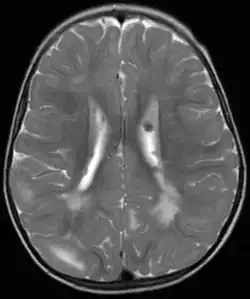

Fehlbildungen und Tumoren des Gehirns

Fehlbildungen und Tumoren des Gehirns werden oft frühzeitig festgestellt. Kortikale glioneuronale Hamartome, die so genannten Tubera (Vorwölbungen) im Bereich der Hirnrinde, gehen häufig mit Epilepsie einher und können kognitive Beeinträchtigungen verursachen, während subependymalen Riesenzellastrozytome und subependymale Knötchen aufgrund ihrer Nähe zum Ventrikelsystem typischerweise zur Entwicklung eines Hydrozephalus führen.